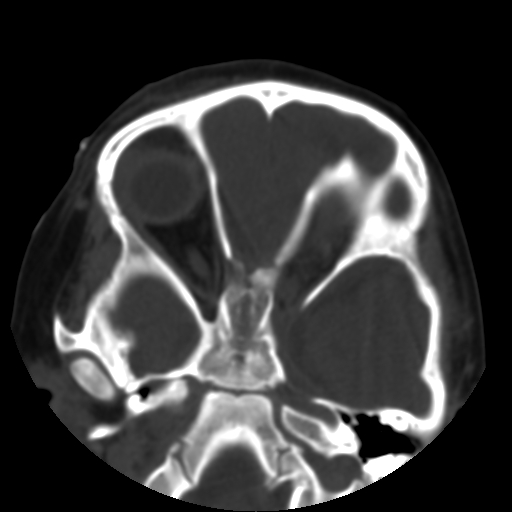

以下是引用深泽交通医院在2009-10-16 8:25:00的发言:[br]右眼环出血伴异物

以下是引用卜一在2009-10-16 15:01:00的发言:[br]右眼球挫裂伤伴异物!

以下是引用拾荒者在2009-10-17 18:38:00的发言:[br]鼻面部皮下积气,右侧睑缘及眼球壁高密度异物影,左侧眼球壁晶状体内侧缘处是圆形低密度影。低密度异物?应提请眼科医生注意。